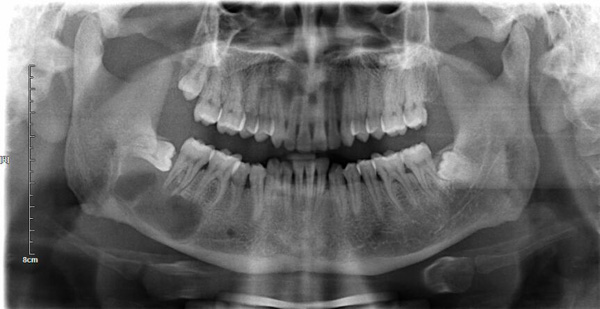

现年35岁的龙先生,本来是一名在外打拼的商人,却突然生命垂危进入重症监护室抢救,差点因此丢了性命,原因竟是一颗“尽头牙”。

龙先生辗转求诊多家医院后来到玉溪市人民医院口腔颌面整形外科,接诊医生检查后诊断为“智齿来源的颌骨囊肿感染引发的颌面部多间隙感染”。感染因为组织间隙和重力影响随着筋膜层移动到了胸肺部,引起了纵膈脓肿,必须给予了颌面部脓肿切开引流。

口腔医生提醒:智齿俗称“尽头牙”,是一颗排列在牙弓最后面的牙齿,人类的祖先在猿人时期,没有太多的工具,需要靠撕咬才能切分食物,所以我们大多数人有32颗牙齿。而随着我们逐渐可以使用更锋利的工具,切分食物已经不再是牙齿的本职工作,而我们的颌骨也因为没有撕咬食物的力量刺激渐渐进化缩小成现在的模样,但大多数人牙齿没有进化消失,从而会有牙弓最后方的智齿埋在骨头里。停留在牙槽骨中的智齿可刺激上皮细胞,使之增殖并分泌液体,当分泌的液体慢慢增多,像气球那样鼓胀起来,就会逐渐形成颌骨囊肿,智齿被包围在囊内。当囊肿发生感染,就会导致颌面部间隙感染,更加严重的,就会像龙先生一样形成胸腔区域的感染,危及生命。